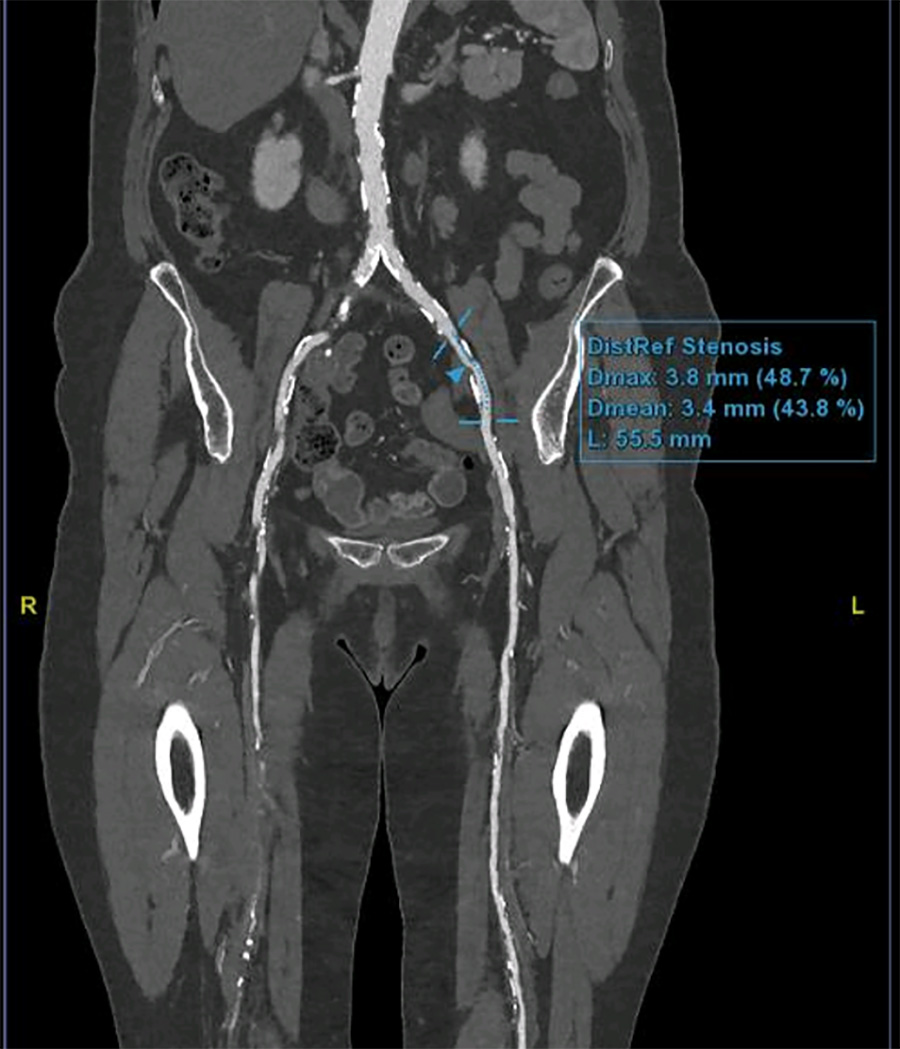

Scanner et Angio-scanner

Le scanner est un examen radiologique utilisant les rayons X, qui permet d’obtenir des images en 3 dimensions de différents organes du corps ; l’angioscanner analyse les vaisseaux de l’organisme, artères et veines, après injection intraveineuse d’un produit de contraste iodé.

Cet examen permet une analyse fine des vaisseaux, et vient le plus souvent en complément d’un échodoppler initial qui aura mis en évidence des anomalies vasculaires

Reconstruction de l’aorte et des artères iliaques et fémorales en angioscanner